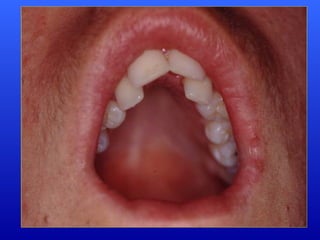

• Palato ogival,

escavado

Palato ogival;

Respirador Bucal Puro:é o individuo com impossibilidade total de respirar pelo nariz. Caracteriza-se resumidamente por: Hipoplasia global da mandíbula, com retrognatismo, hipomentonismo e grande retrusão da arcada inferior Palato ogival; Alongamento, protusão da arcada superior; Lábio superior curto e espesso; Exposição excessiva dos incisivos superiores quando em repouso; Nariz curto vertical.

Respirador Misto: apresentaalternância de permeabilidade da via aérea e obstrução nasal, conferindo-lhe características próprias. Retrognatismo discreto com relação aceitável entre as arcadas; Palato ogival; Alongamento e protusão da arcada dentária superior; Lábio superior alongado; Nariz curto.